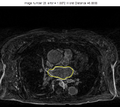

Results

The example of extracted ridges is shown in the Figure 1. The connected boundary is shown in the Figure 2. For the tested volumes, when comparing the obtained boundary with expert's manual segmentation, the average distance error is about 2 pixels. The results of GVF active contour approach are shown in the Figures 3-5. The bright gray contour is the expert's segmentation, and yellow contour is the result of our algorithm. The average distance error there is less than 2 pixels.